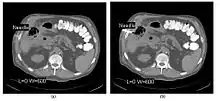

- CT Fluoroscopy (CTF) has also been referred to as Continuous CT or Real-Time CT since it involves generating tomographic images at sufficiently high frame rates to allow guidance of needle placement in small or deep-seated lesions. Applications can include biopsy of thoracic lesions, biopsy/drainage of pelvic lesions, vertebroplasty and drainage/aspiration of intracranial haematomas. The advantages of CTF include increased target accuracy and reduced procedure times[45].

- The major difference to a conventional CT system is that high speed reconstruction techniques are applied, and that an operator panel, exposure footswitch and image monitor are installed in the scanning room for use by the interventionist. Controls are generally available for table movement, gantry tilt, laser grid definition and fluoroscopic factors. The other significant operational change relates to the choice of tube current which is typically 30-50 mA in CTF. This should be compared with typical screening currents used in conventional fluoroscopy of up to 5 mA, so that CTF can be regarded as a high dose procedure. In this context, additional beam filtration can be introduced automatically for CTF procedures to reduce patient exposure by up to 50%, for example. Furthermore, the use of protective gloves and needle holders can reduce the radiation exposure to the hands of the interventionist.

- The value of N is typically 30o, 45o or 60o, with frame rates of 12, 8 and 6 frames per second, respectively. In the case of 60o updates and 6 frames per second, the delay between each image is 0.17 seconds. A Last-Image-Hold (LIH) technique can be used while the image is being updated with the resulting time lag being considered by the interventionist in terms of biopsy technique. Example images are shown in Figure 7.15.11. The display of three adjacent slices of thickness 5 mm with MDCT scanning can be used to improve visual feedback to the interventionist as the needle progresses. In addition, multi-planar reconstructions (MPR) and volume rendered 3D images can be used to enhance fine control.